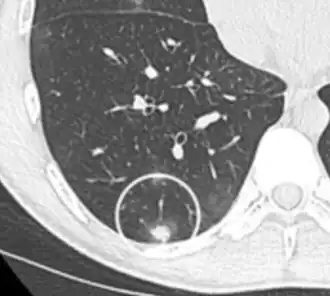

- A lung nodule abutting a pulmonary cyst is a rare finding, yet indicating cancer.[9]

- Bubble-like lucencies in the nodule indicate cancer:[9]